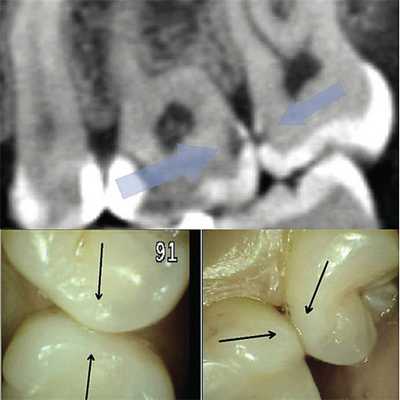

Это связано с тем, что при контактном кариесе площадь разрушенной эмали зачастую невелика, находится в контакте с соседним зубом или ниже экватора, и поэтому дефект остается перекрытым эмалью, сохраненной на окклюзионной, вестибулярной и оральной поверхности зуба (рис. 1).

Рис. 1. При обследовании контактного пункта зубов 26, 27 (нижний фрагмент) кариес визуально не определяется; на сагиттальном реформате компьютерной томограммы в области проксимальных к контактному пункту поверхностей тех же зубов деминерализация очевидна.